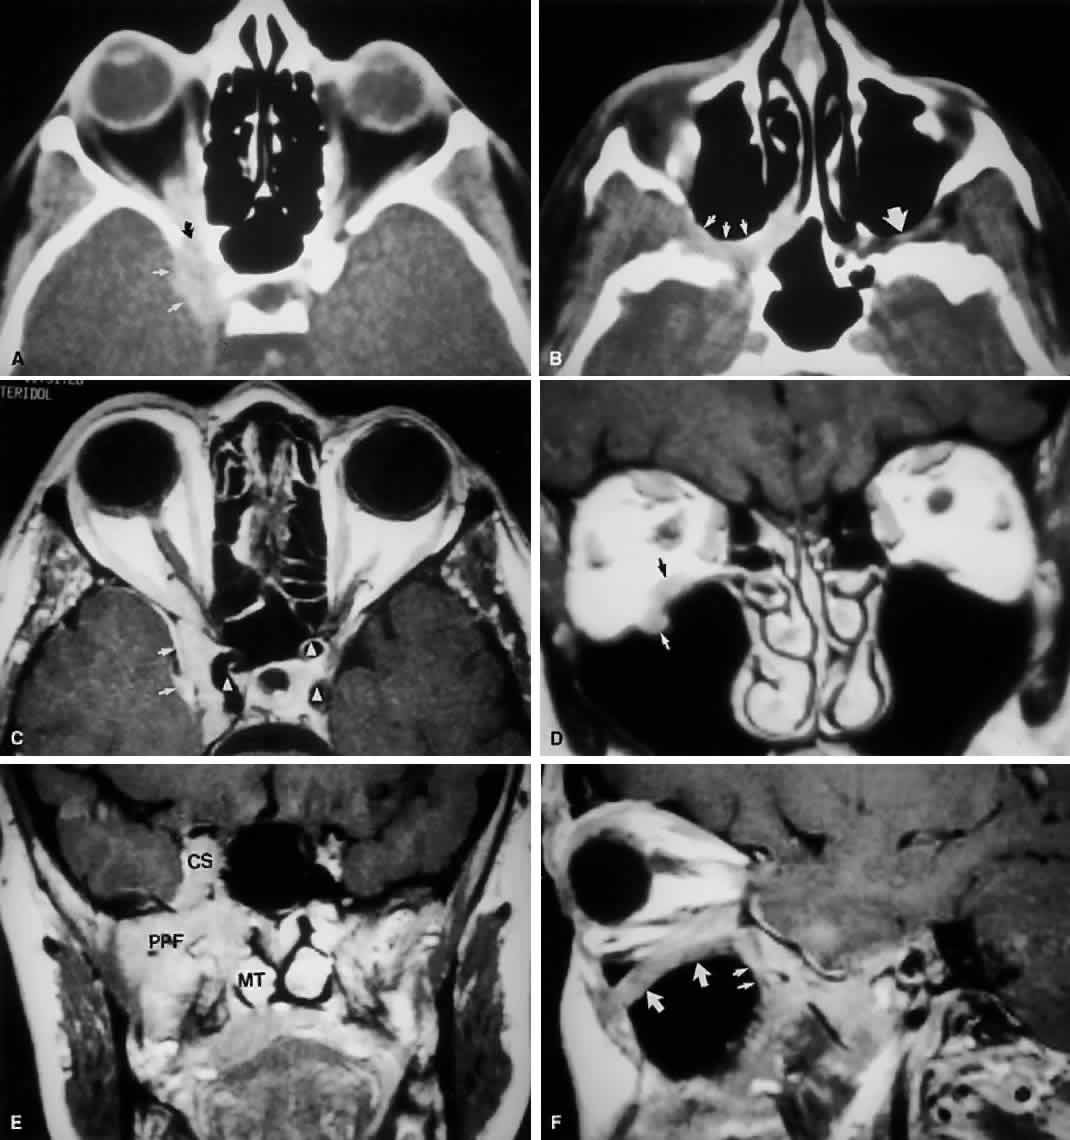

Fig. 9. An orbital lymphoma involving the skull base provides accentuation of the apical spaces of the orbit. A. On this axial CT, the lesion infiltrates the CS, causing bulging and local invasion of its lateral dural wall (small arrows). Invasion into the orbital apex through the superior orbital fissure (curved arrow) is seen. Note that the patient is slightly rotated in the scanner, because the anterior clinoid and optic canal are visualized on the uninvolved side. B. More inferiorly, the mass has invaded the pterygopalatine fossa (small arrows), located just posterior to the maxillary sinus. On the uninvolved side (large arrow), the fossa has areas of radiolucency, indicating the fat that normally occupies this space. C. Axial MRI, T1-weighted image with gadolinium but without fat suppression. The carotid siphon is seen within each CS as a flow void (arrowheads). Once again, note the inflamed lateral dural wall of the CS and local invasion of the brain parenchyma (small arrows).D. Coronal T1-weighted MR image. The inferior rectus muscle is labeled with a black arrow. The lymphoma has infiltrated the infraorbital canal (white arrow) within the orbital floor. E. Coronal MRI of the orbital apex shows infiltration from the CS to the pterygopalatine fossa (PPF). Because there is no direct communication between these spaces, the lesion must have spread through the superior orbital fissure into the orbital apex, then through the inferior orbital fissure. MT, middle turbinate. The lucency just above the CS is the anterior clinoid process, with the optic nerve within its canal seen as an opacity between the clinoid and the sphenoid sinus. F. Parasagittal MRI shows lymphomatous invasion of the pterygopalatine fossa just behind the posterior wall of the maxillary sinus (small arrows). Note the thickening of the infiltrated infraorbital canal (large arrows) as it travels anteriorly to exit about 1 cm below the inferior orbital rim.